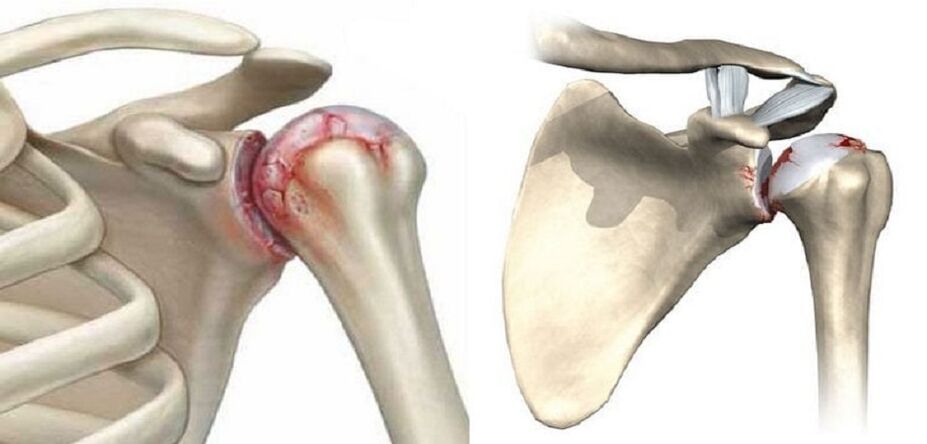

L'arthrose de l'articulation de l'épaule est une modification douloureuse, la destruction du tissu cartilagineux. À mesure que la maladie progresse, vous maigrissez. Par la suite, les zones endommagées sont remplacées par des ostéocytes. Ce processus destructeur est dû à une nutrition insuffisante des chondrocytes et à une mauvaise production de substances telles que l'élastine et le collagène. Pour arrêter la destruction, il est important de diagnostiquer la maladie à temps. Consultez un médecin qui vous prescrira un traitement réparateur complet et compétent.

- Formation d'ostéophytes ;

Au deuxième stade du développement de la pathologie, une procédure d'arthroscopie est prescrite. Il s’agit d’une méthode de recherche invasive. Au cours de cette procédure, un endoscope est inséré dans l’alvéole de l’épaule. Simultanément à l'étude de l'état des tissus, les excroissances osseuses sont éliminées.